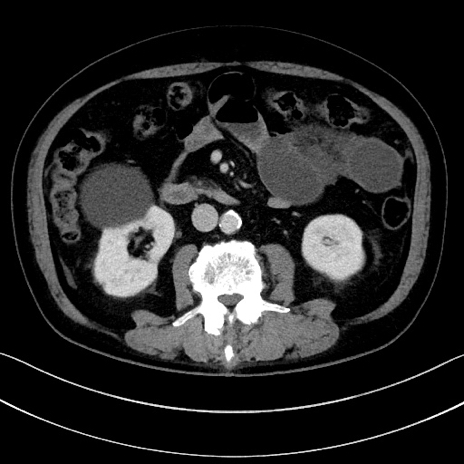

冠状断像

【症例】70歳代男性

【主訴】腹痛

【現病歴】今朝から腹痛あり。全体的に痛い。特に左上の方。排ガスが今日はない。冷や汗が出る。

【既往歴】直腸癌術後

【身体所見】左側腹部〜上腹部に圧痛あり。腹膜刺激症状明らかなではない。軽度反跳痛。左下腹部に術後瘢痕あり。

【データ】WBC 7700、CRP 0.02